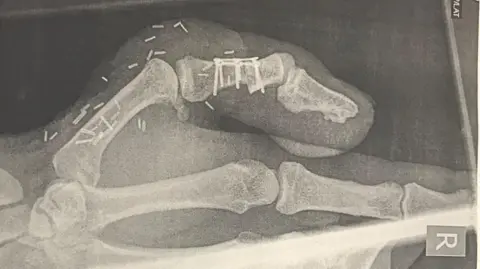

News imageSupplied An X-ray of the toe thumb post surgerySupplied

A series of operations on the foot and hand took about 10 hours